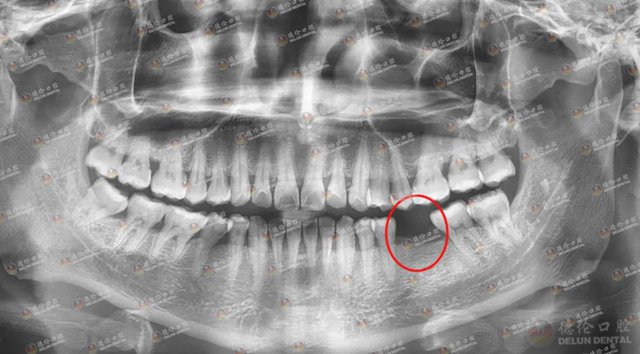

30余岁的谢先生左下6患龋齿,由于没及早治疗,蛀牙被蛀得牙冠基本缺失,只剩下比较脆弱的残根组织,没有办法通过根管治疗治愈,只能作拔除处理。

谢先生左下6缺牙多年